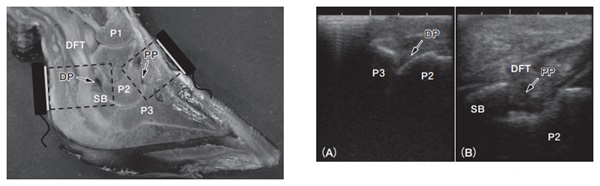

In my experience, and as supported by veterinary studies, ultrasound can identify abnormalities that would otherwise be missed. For instance, in a study involving ten cattle with confirmed infectious arthritis and limb amputations, ultrasonographic findings were compared with conventional methods and post-mortem analysis. The results confirmed that ultrasound reliably detected signs of joint infection.

The ultrasound examination revealed several consistent indicators across the infected limbs:

Enlarged joint capsule: A hallmark sign, appearing as an anechoic (dark) area on the image, indicating fluid accumulation.

Joint capsule measurements:

Dorsal side: average thickness of 7.9 mm (range: 5.8–12.3 mm)

Palmar/plantar side: average thickness of 13.8 mm (range: 10.8–16.4 mm)

Other abnormalities observed on palmar/plantar images:

Presence of hoof abscesses

Torn deep digital flexor tendon

Osteomyelitis of the distal sesamoid bone

Excess synovial fluid in the tendon sheath

These findings were consistent with joint infections confirmed through necropsy. Importantly, such detailed visualization is not possible with radiography or clinical examination alone.